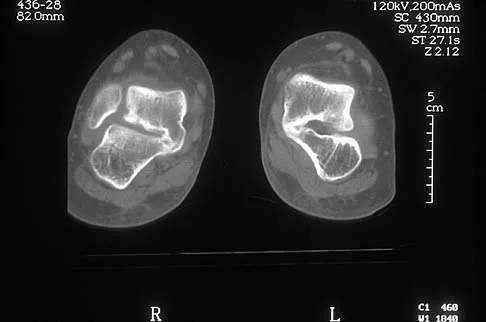

Question 51High Yield

A 12-year-old boy has had progressive pain and flatfeet for the past year. Pain is increased with weight-bearing activities. Examination reveals that subtalar motion is absent. On standing, the patient has obvious hindfoot valgus and loss of the normal arch bilaterally. Plain radiographs are shown in Figures 43a through 43c, and a CT scan is shown in Figure 43d. What is the most likely diagnosis?

Explanation

The axial views show fusion of the talus and calcaneus at the medial facet (talocalcaneal coalition). Peroneal spastic flatfoot is a descriptive term applying to the symptoms of painful flatfoot associated with apparent peroneal spasm and is sometimes caused by tarsal coalition; however, this is not the most appropriate diagnosis for this patient. Flexible flatfoot with a short Achilles tendon often causes symptoms similar to the ones listed above, but subtalar motion should be normal. A diagnosis of calcaneonavicular coalition can be made based on plain oblique views of the foot but is not seen in these views. Posterior tibial tendon dysfunction in the absence of other pathology is uncommon in children. Vincent KA: Tarsal coalition and painful flatfoot. J Am Acad Orthop Surg 1998;6:274-281.